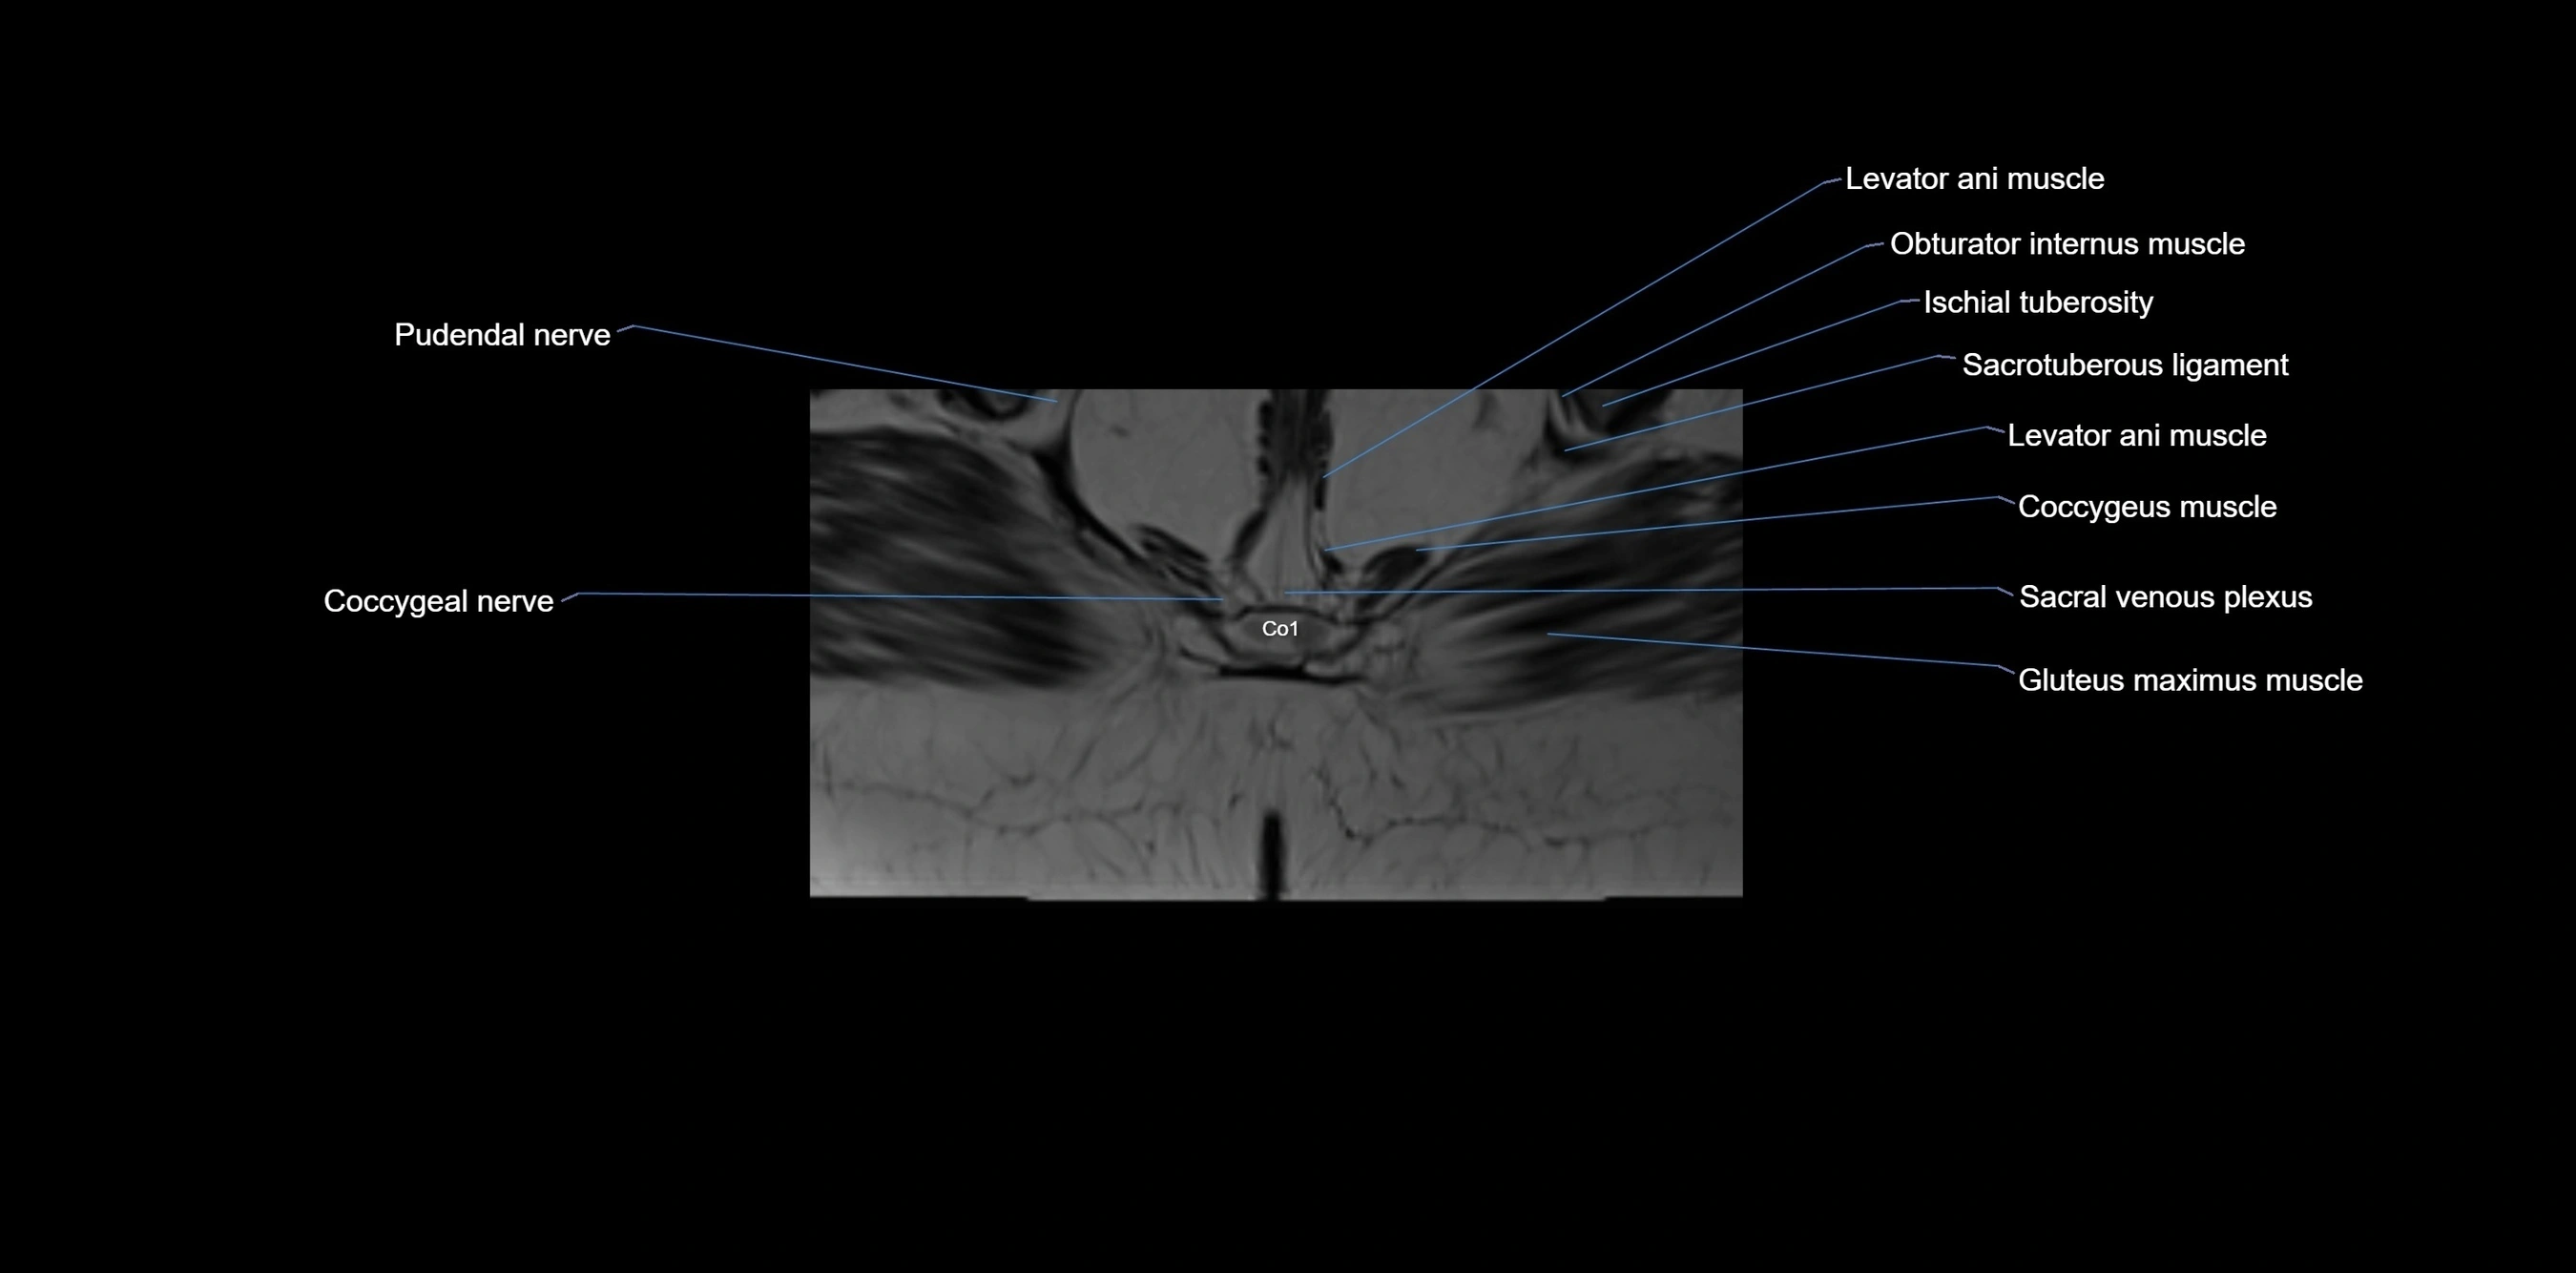

CT VRT image

image